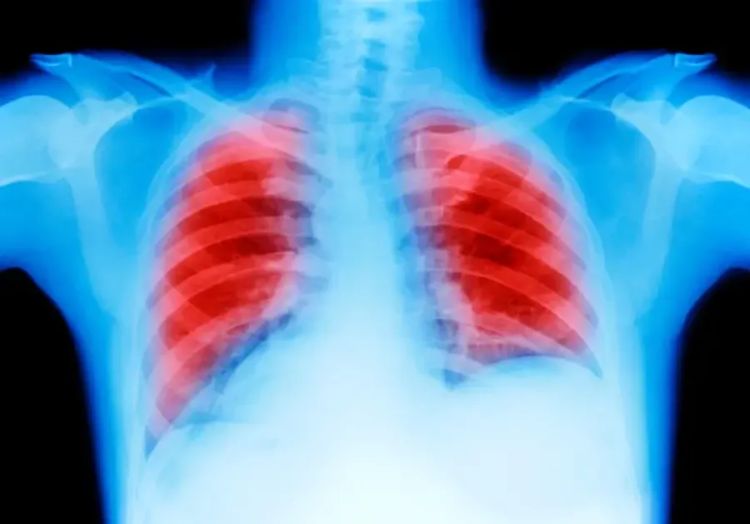

O diagnóstico da pneumonite é feito por um médico clínico geral ou pneumologista através da avaliação dos sintomas, histórico de saúde do paciente, exame físico com a escuta dos pulmões ou por exames para atestar a saúde dos pulmões, como raio-X de tórax, tomografia computadorizada e exames laboratoriais.